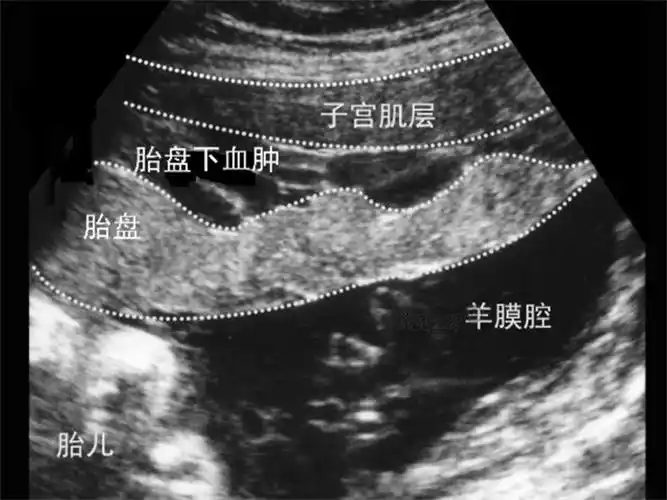

胎盘早剥的症状及危害

症状图片胎盘早剥血肿超声图片胎盘早剥诊断图胎盘早剥诊断图片胎盘早